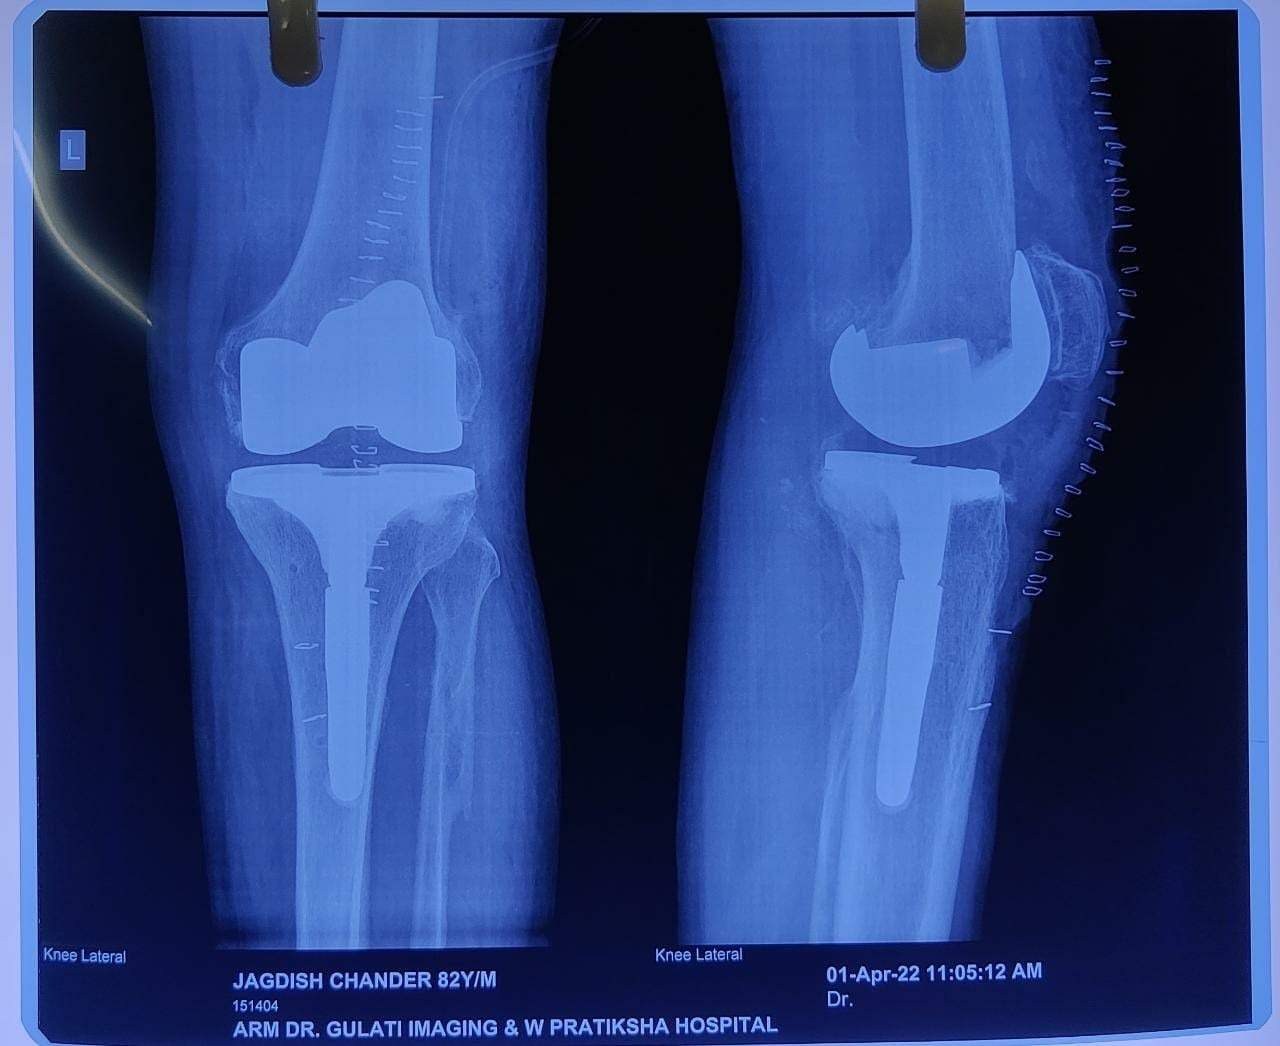

Post Operative